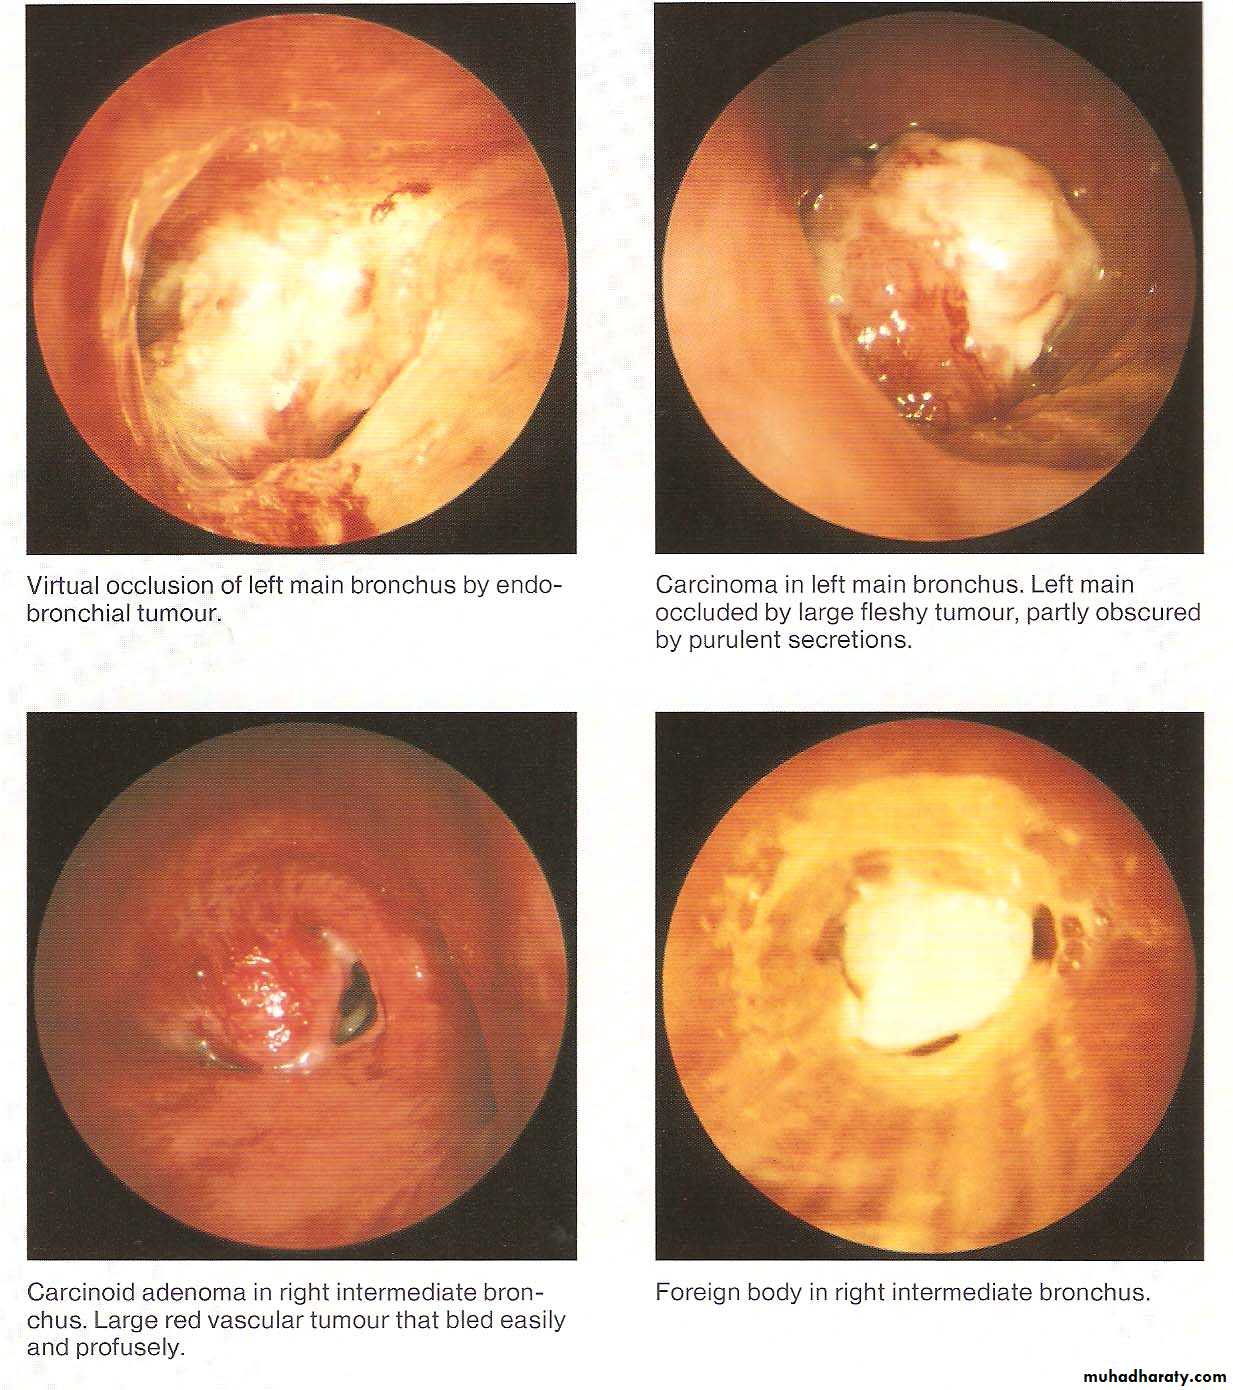

• Abnormal Bronchoscopic Findings

Diagnostic indications include tissue diagnosis, detection and staging of lung malignancy, evaluation of diffuse lung diseases like sarcoidosis and idiopathic interstitial pneumonias, pulmonary inspection of burn patients, identification of organisms infecting the respiratory tract and lungs.

As a therapeutic modality, bronchoscopy is used to place stents to protect airways vulnerable to collapse or occlusion, to remove foreign bodies or masses, to treat early stage endobronchial malignancy.